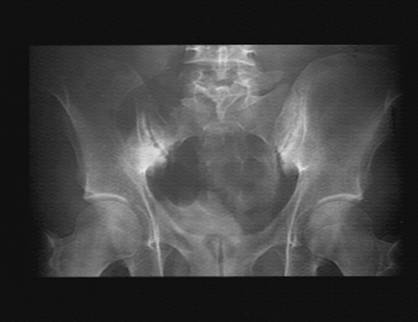

Décrivez l'iconographie N°1, que

suspectez-vous ?

Décrivez-le. Avez-vous besoin

d'un autre examen morphologique ?